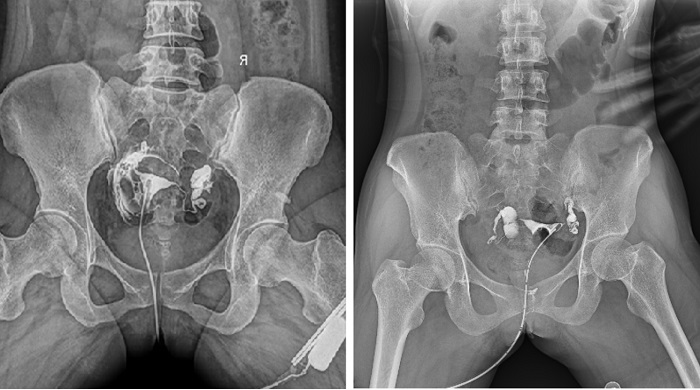

輸卵管造影檢查可根據(jù)造影劑在輸卵管及盆腔內(nèi)的顯影情況了解輸卵管是否通暢、阻塞部位及宮腔形態(tài),是超聲、CT、核磁、宮腔鏡、腹腔鏡、輸卵管鏡等所無法替代的。作為目前普放領(lǐng)域最先進(jìn)的影像設(shè)備,多功能動態(tài)DR進(jìn)行子宮輸卵管造影檢查,大大超越了過去的檢查技術(shù),更加精準(zhǔn)、便捷、高效。

相較于傳統(tǒng)胃腸機(jī),動態(tài)DR矩形采集面積大,一次曝光即可顯示整個盆腔,大幅減少觀察時間,可控的瞬時照射避免受檢者吸收過多的X線,對育齡期女性的檢查尤為重要。毫秒級時間內(nèi)高清點片,可以在造影劑流動的過程中完成拍片,抓拍到關(guān)鍵圖像,更加清楚地了解到管腔的具體通暢情況及堵塞部位,對檢查及診斷有非常重要的價值。

子宮輸卵管造影

此外,應(yīng)用動態(tài) DR 進(jìn)行子宮輸卵管造影,還可以在加壓推注下,使部分輸卵管輕、中度堵塞的患者得以通暢,起到一定的治療作用。